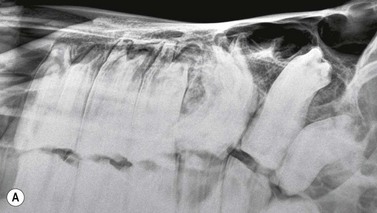

Fig. 13.35 Oligodontia. The pony in (A) has anodontia of 308, 408 and 108, although the deciduous remnant (‘cap’) of one lower 08 is still present.

Radiograph courtesy of P.M. Dixon.

image

The pony in (B) has only 5 teeth in both mandibular rows, with large overgrowths of the upper 10s and 11s and secondary diastemata formation between the upper 09s and 10s.